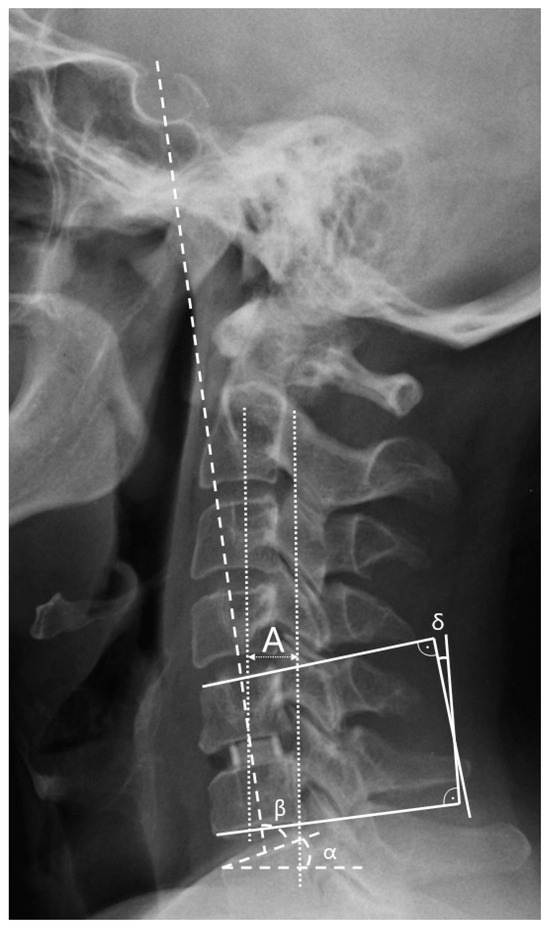

| C2–C7 saggital vertical axis (cSVA) | The distance from the posterior superior corner of C7 to the plumbline from the centroid of C2. |

| Spinocranial angle (SCA) | The angle is measured as the deviation between the slope of C7 and the straight line that connects the midpoint of the C7 end plate to the midpoint of the sella turcica. |

| C7 slope | The angle between a horizontal line and the superior endplate of C7. |

| C2–C7 lordosis | The angle between the C2 and C7 lower endplates. |

| Segmental angle | The Cobb’s angle between the lower endplates of the fused vertebrae. |